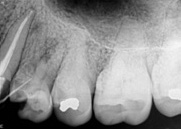

antes depois